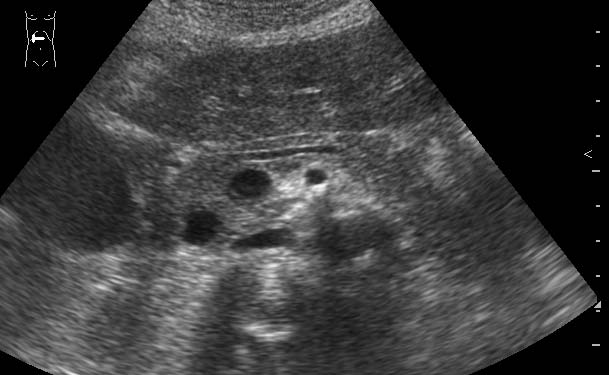

Молодая женщина с болями в животе.

Продольная сонограмма панкреас

Какое заключение можно сделать по этой сонограмме?

Какова дальнейшая тактика ведения больной?

Очаговые образования головки ПЖ (кисты?) Рек-но КТ.

Жаль нет снимка во взаимоперпендикулярной плоскости.Можно предположить аневризму брюшного отдела аорты.

По моему это расширенный Вирсунгиев проток,нужно исключать патологию дуоденального сосочка-ФГС